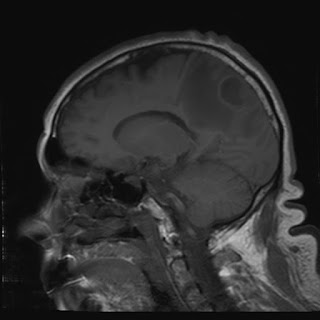

Caso neurorradiología

Paciente de 60 años con cuadro de 1 semana de evolución consistente en tropiezos frecuentes y alteración en la movilidad del miembro

inferior derecho. No refiere

cefalea u otros síntomas asociados, no pérdida de peso, no náuseas o emesis, no

sudoración nocturna. Antecedentes de hipertensión arterial y diabetes.

Resonancia magnética